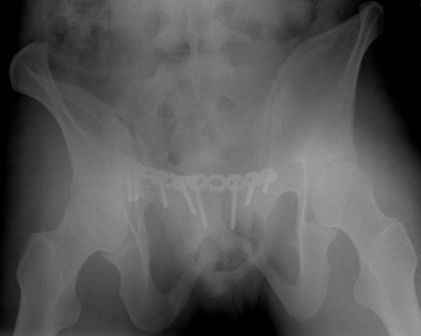

Серия до- и послеоперационных снимков этой пациентки. Хотя бы post factum обсудить. Не знаю, что можно сделать с задними отделами стержневым аппаратом, но три крепких парня открытым путем с помощью "волшебных" слов еле-еле смогли отрепонировать - сзади все было очень ригидно!

я бы остановился на передней раме, операция - 30 мин, в таком варианте вроде бы репозиция - ничего, но когда давать нагрузку, ведь в лонном сочленении тоже есть подвижность? а если не давать - зачем операция?